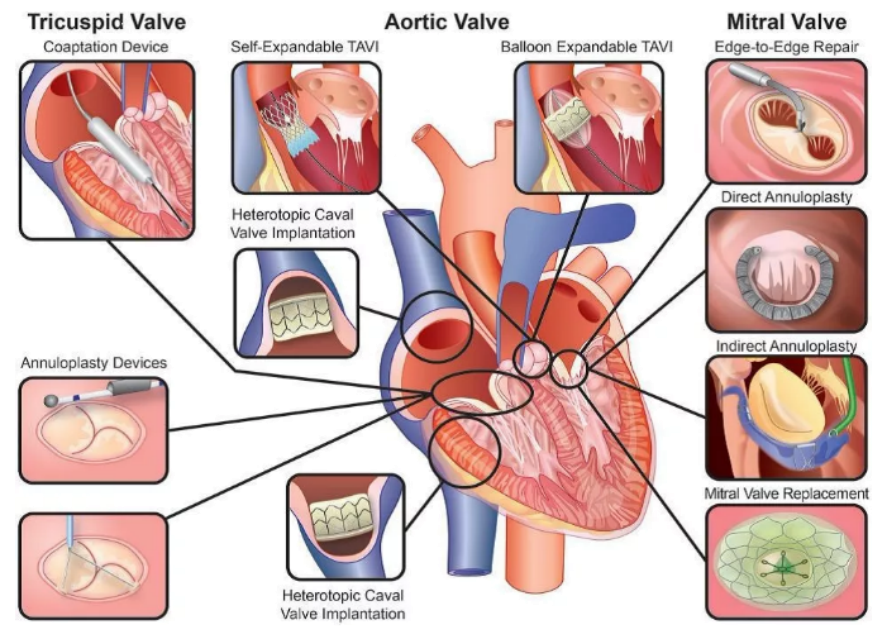

二尖瓣关闭不全(Mitral Regurgitation,MR)是一种常见心脏瓣膜病,其发病率随年龄增长呈逐渐增加趋势,并伴有较高的再住院率和死亡率。在中国老年瓣膜性心脏病住院患者队列研究数据中发现,MR在心脏瓣膜病比重较大,介入治疗亟需发展。长期以来,外科手术是治疗MR的唯一标准。近年来,TEER逐渐发展成熟,成为MR手术的一种替代方案。然而,由于二尖瓣反流从操作、器械、病人评估等方面存在一定的难度,二尖瓣修复技术开展的数目比经导管主动脉瓣置换术要低得多。

既往发表在《European Heart Journal》文章研究结果显示,早期积极行经导管二尖瓣缘对缘修复技术(Transcatheter edge-to edge repair, TEER)能显著改善患者的远期预后,降低死亡率。基于此,经MDT团队讨论后,最终团队决定尽早行TEER术,与患者家属进行充分沟通后,拟用MitraClip行经导管二尖瓣缘对缘修复手术。